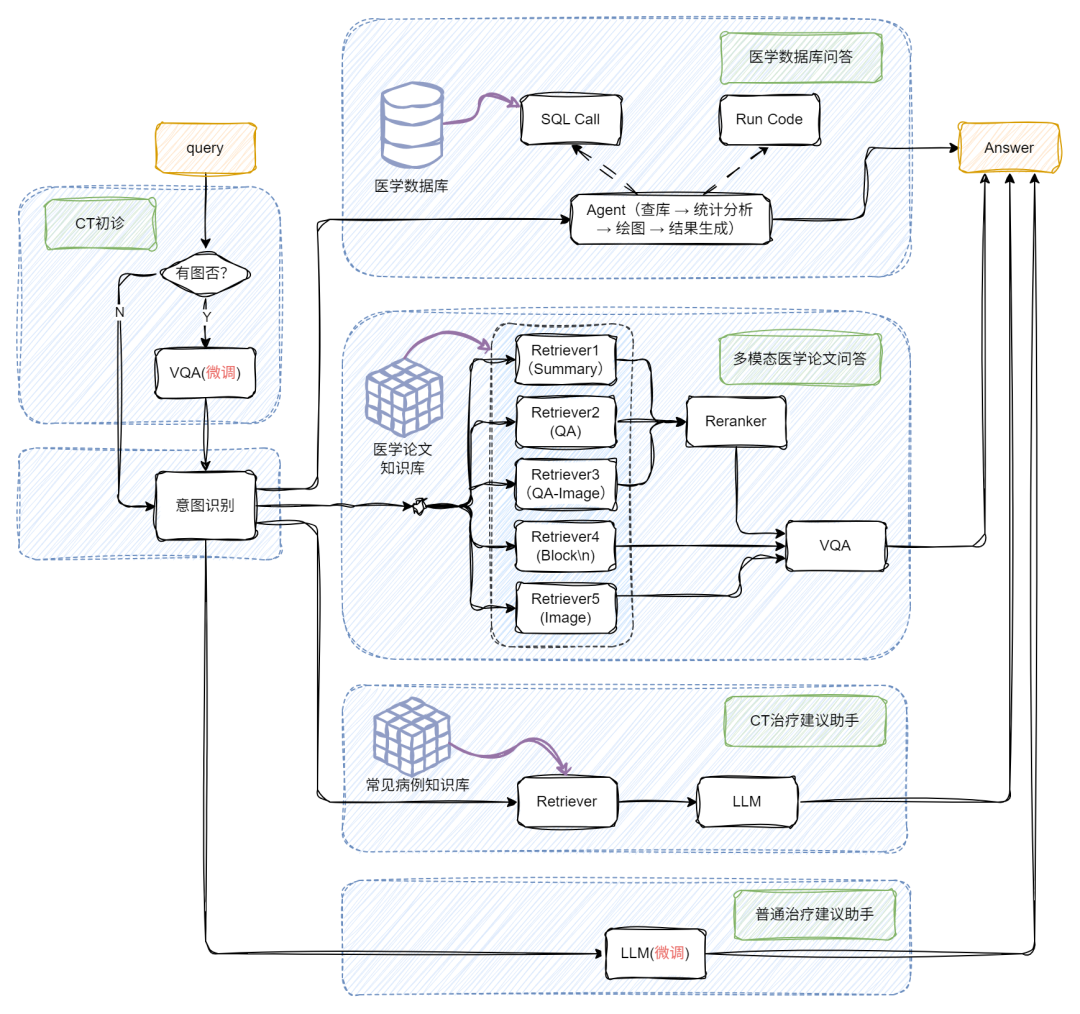

下图和视频效果是我们今天的目标!涉及多路召回多模态RAG、多模态问答、Chat-BI、Agent、LLM微调、多模态模型微调等等。让我们开始吧!

通过前面的探索,我们已经了解了朴素 RAG 如何让大模型具备“查资料再回答”的基础能力,也见证了多模态 RAG 通过图文融合实现的“感官升级”。但当实际应用场景涉及“医院年度病例统计分析”、“科研文献数据可视化呈现”等需求时,单纯的多模态处理仍显不足 —— 这类场景既需要解析医学影像、病历文本等非结构化数据,又要对接数据库完成指标计算、图表生成等 BI任务。

如何让 RAG 系统同时驾驭多模态理解与结构化数据分析?接下来要展开的多模态 + BI复杂架构实战,正是为解决这类“既要又要”的高阶需求而生,我们将在朴素 RAG 基础上层层叠加关键模块,最终打造出能同时处理影像诊断、数据统计、图表生成的全能型 AI 助手!

当用户提问中包含图片时,系统会自动触发 VQA,对图像进行结构化信息提取,挖掘上下文关键内容;若没有图像,就跳过这步,直接进入文本处理环节,效率UPUP!

接下来,系统通过意图识别模块,将不同类型的问题智能分流:

📌论文问答? 走传统 RAG 路线!向量检索+大模型生成,精准提取相关文献内容。

📌统计问答? 开启 SQL 模式!从提问中抽取结构化信息(如指标、维度、过滤条件),自动生成 SQL 查询,查询结果再由大模型“翻译”成自然语言,一目了然!

基于前面多模态与 BI 能力的深度融合实践,我们进一步将 RAG 系统向医疗垂直场景做了进阶升级 —— 如今这套架构不仅能处理常规的文本问诊,更能通过 VQA 模块与医学知识库的联动,实现 CT 影像解析与智能诊断辅助的核心能力,打通了从临床咨询到辅助决策的全流程服务闭环。下面就带大家看看这套融合多模态理解、数据统计与专业知识的医疗 RAG 系统是如何落地的!